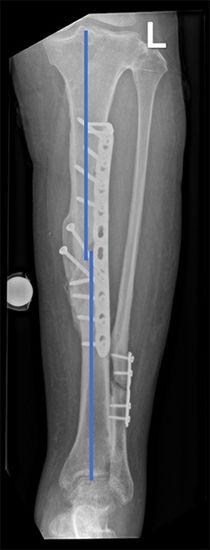

Bild: Universitätsklinik Balgrist

In der klinischen Untersuchung werden die Schmerzen lokalisiert und meist schon die Fehlstellungen erkannt. Wichtig dabei ist, auch auf mögliche Muskelverkürzungen zu achten. Röntgenbilder helfen, die Fehlstellung des Knochens zu erkennen. Dabei ist es wichtig, immer mindestens zwei Ansichten (Bilder in 2 Ebenen, gerade und seitlich) aufzunehmen, die möglichst senkrecht aufeinander ausgerichtet sind. Ansonsten erkennt man z. B. in einem seitlichen Röntgenbild nicht, wie sich die Fehlstellung von vorne betrachtet darstellt.

Eine genaue Analyse der Fehlstellung gelingt nur mittels dreidimensionaler Bildgebung. Das derzeit etablierte Verfahren dazu ist ein Schichtröntgen (Computertomographie – CT) des Unterschenkels. Mit Hilfe von an der Universitätsklinik Balgrist entworfenen Programmen, sind wir in der Lage, mittels CT ein dreidimensionales Modell des Beins zu erstellen *. Ein gespiegeltes Modell des anderen, gesunden Beins kann als Vorlage für das Bein mit der Fehlstellung dienen *.